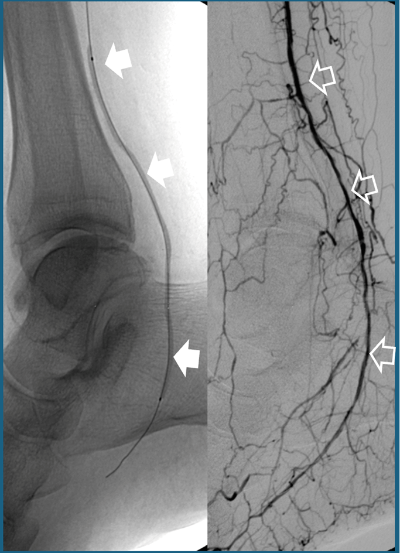

- Angioplasty with or without stenting: A catheter is used to dilate the blocked artery (Fig. 1). If this is not sufficient to keep the vessel open, a small metal mesh (stent) is placed to maintain patency.

Fig.1. A) Balloon catheter angioplasty (solid white arrows) of an occluded distal leg vessel.

B) Final result showing vessel reopening (empty white arrows).